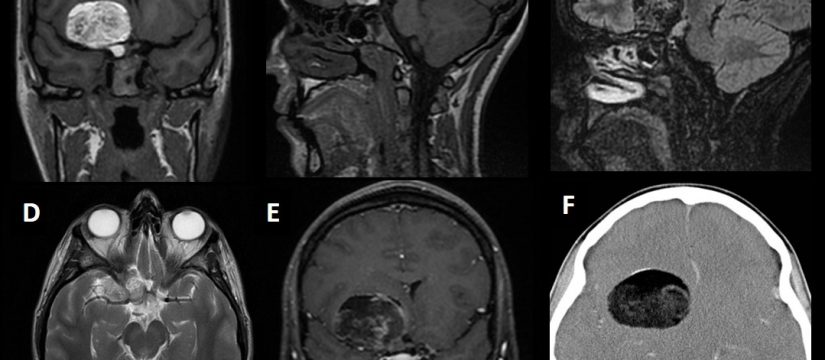

Historia Clínica

Varón de 40 años con esclerosis múltiple remitente-recurrente ya conocida, que consulta por disartria de varios días de evolución.